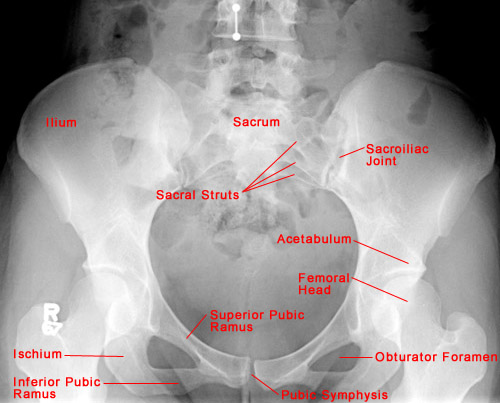

AP view of normal pelvis

• The five bones that comprise the pelvis are the ilium, ischium, pubis, sacrum, and coccyx.